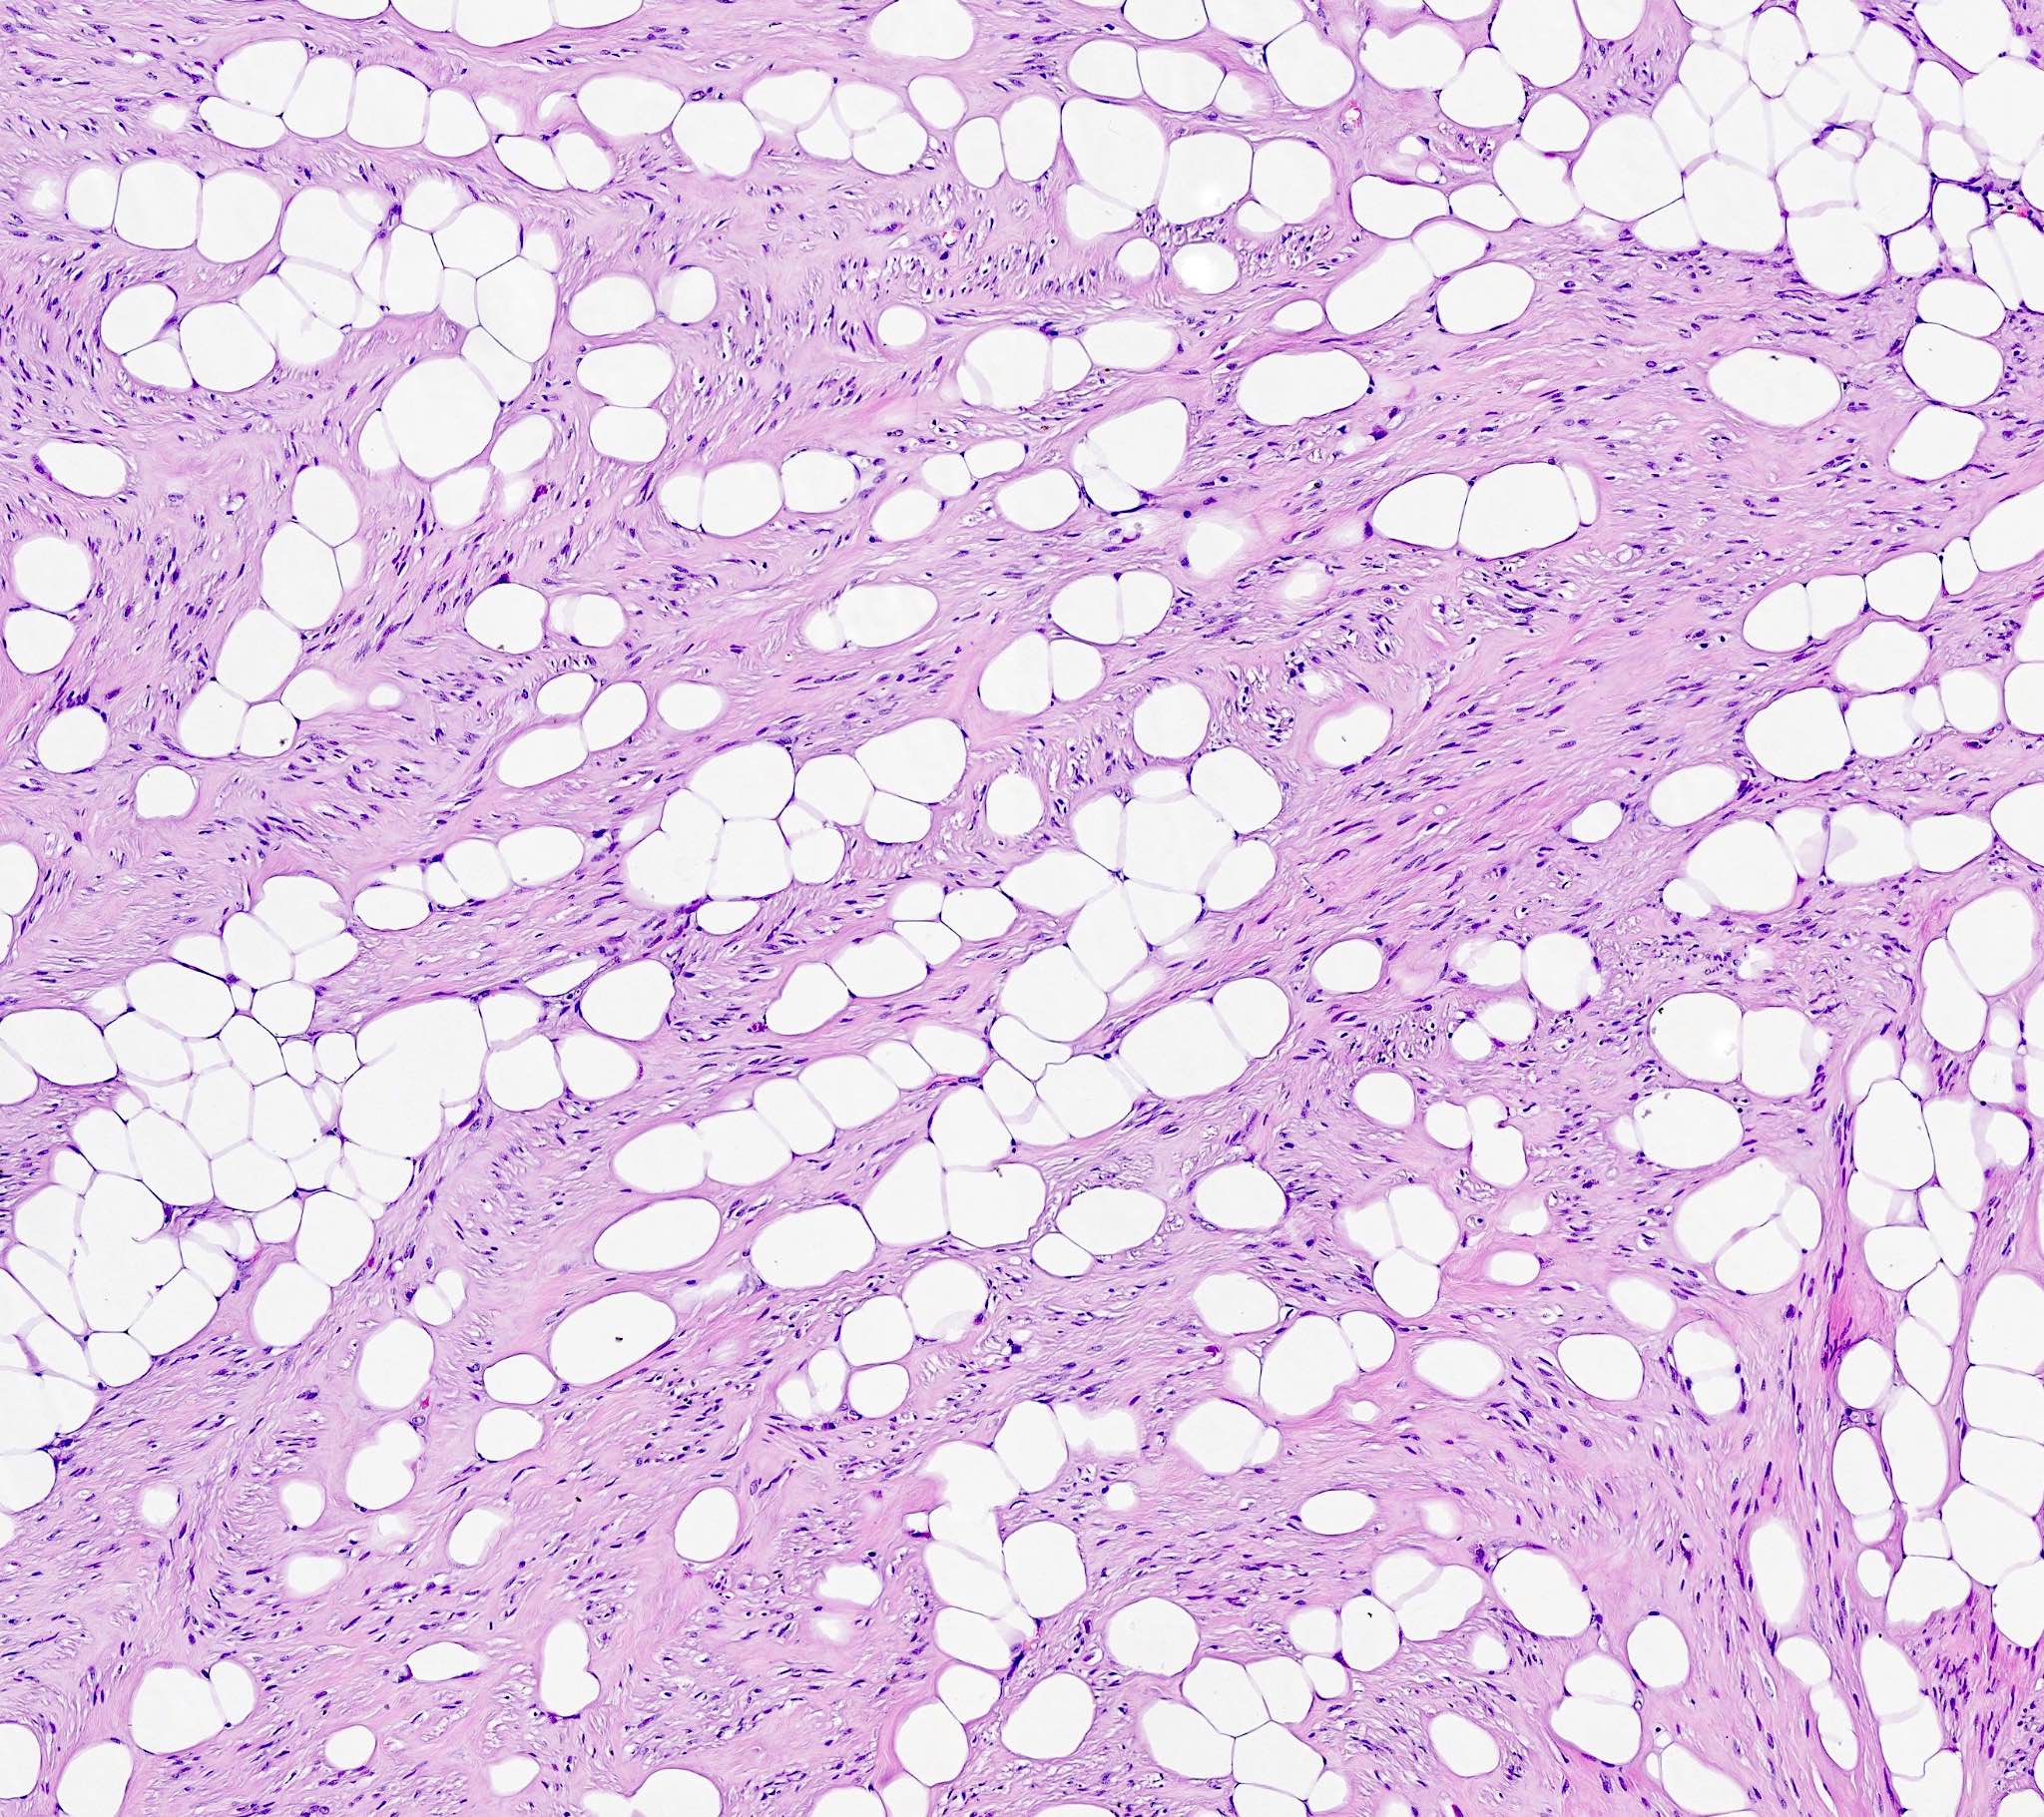

- Lipoleiomyoma:

- Tumor composed of smooth muscle cells mixed with mature adipocytes (variable quantity)

Microscopic (histologic) images

Contributed by Sabrina Croce, M.D., Ph.D., Kristina Doytcheva, M.D., Jennifer A. Bennett, M.D. (Case #508) and @Andrew_Fltv on Twitter